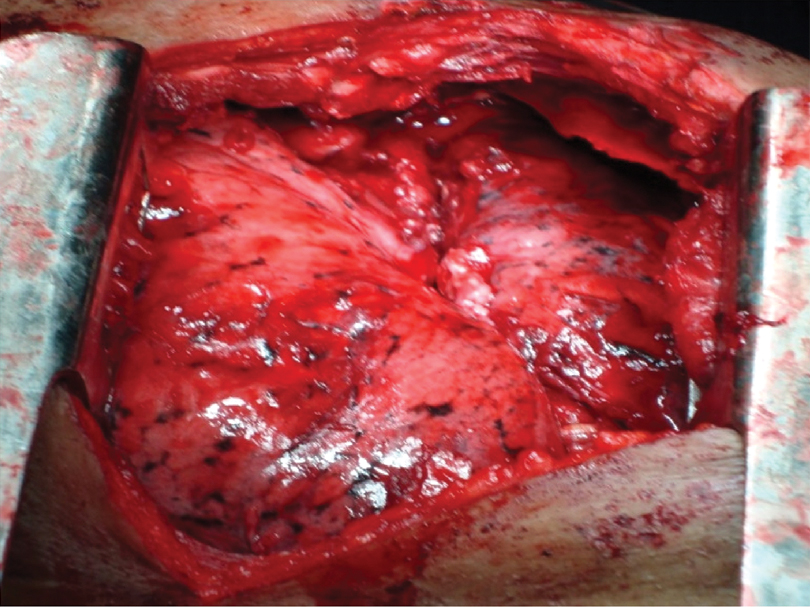

In present study, the first incision of 1-1.5 cm was usually placed between 4th to 7th intercostal space in mid axillary line and 10 mm trocar inserted; 10 mm (zero degree) video thoracoscope inserted and the working ports (5 or 6 mm) were inserted under vision to achieve triangulation and facilitate manipulation of the instruments. Tissue/fluid was sent for culture/sensitivity and histopathological analysis. Loculations were broken and plaques were removed using both blunt and sharp dissections. Special attention was given to clear the costophrenic sulcus in order to prevent adhesion related impairment of diaphragmatic mobility [Table/Fig-3].

If lung expansion was found to be inadequate after debridement then decortication was done. Additional ports were inserted to aid decortication. If decortication was also found to be inadequate, procedure was converted to open thoracostomy. The cavity was thoroughly inspected for any leaks or bleeding or any injury to the lung parenchyma [Table/Fig-4].